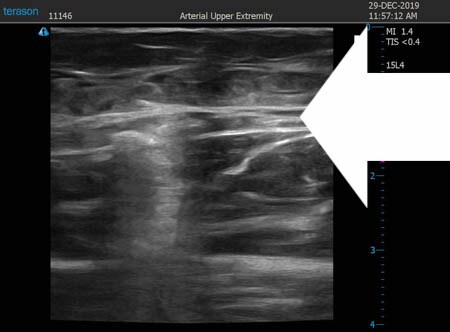

いつものように3Dタッチビュー(超音波)で

皮下脂肪層を評価してみましょう。

左太もも前面。

↓ ↓ ↓

上の画像の部分の皮下脂肪層をつまんでみましょう。